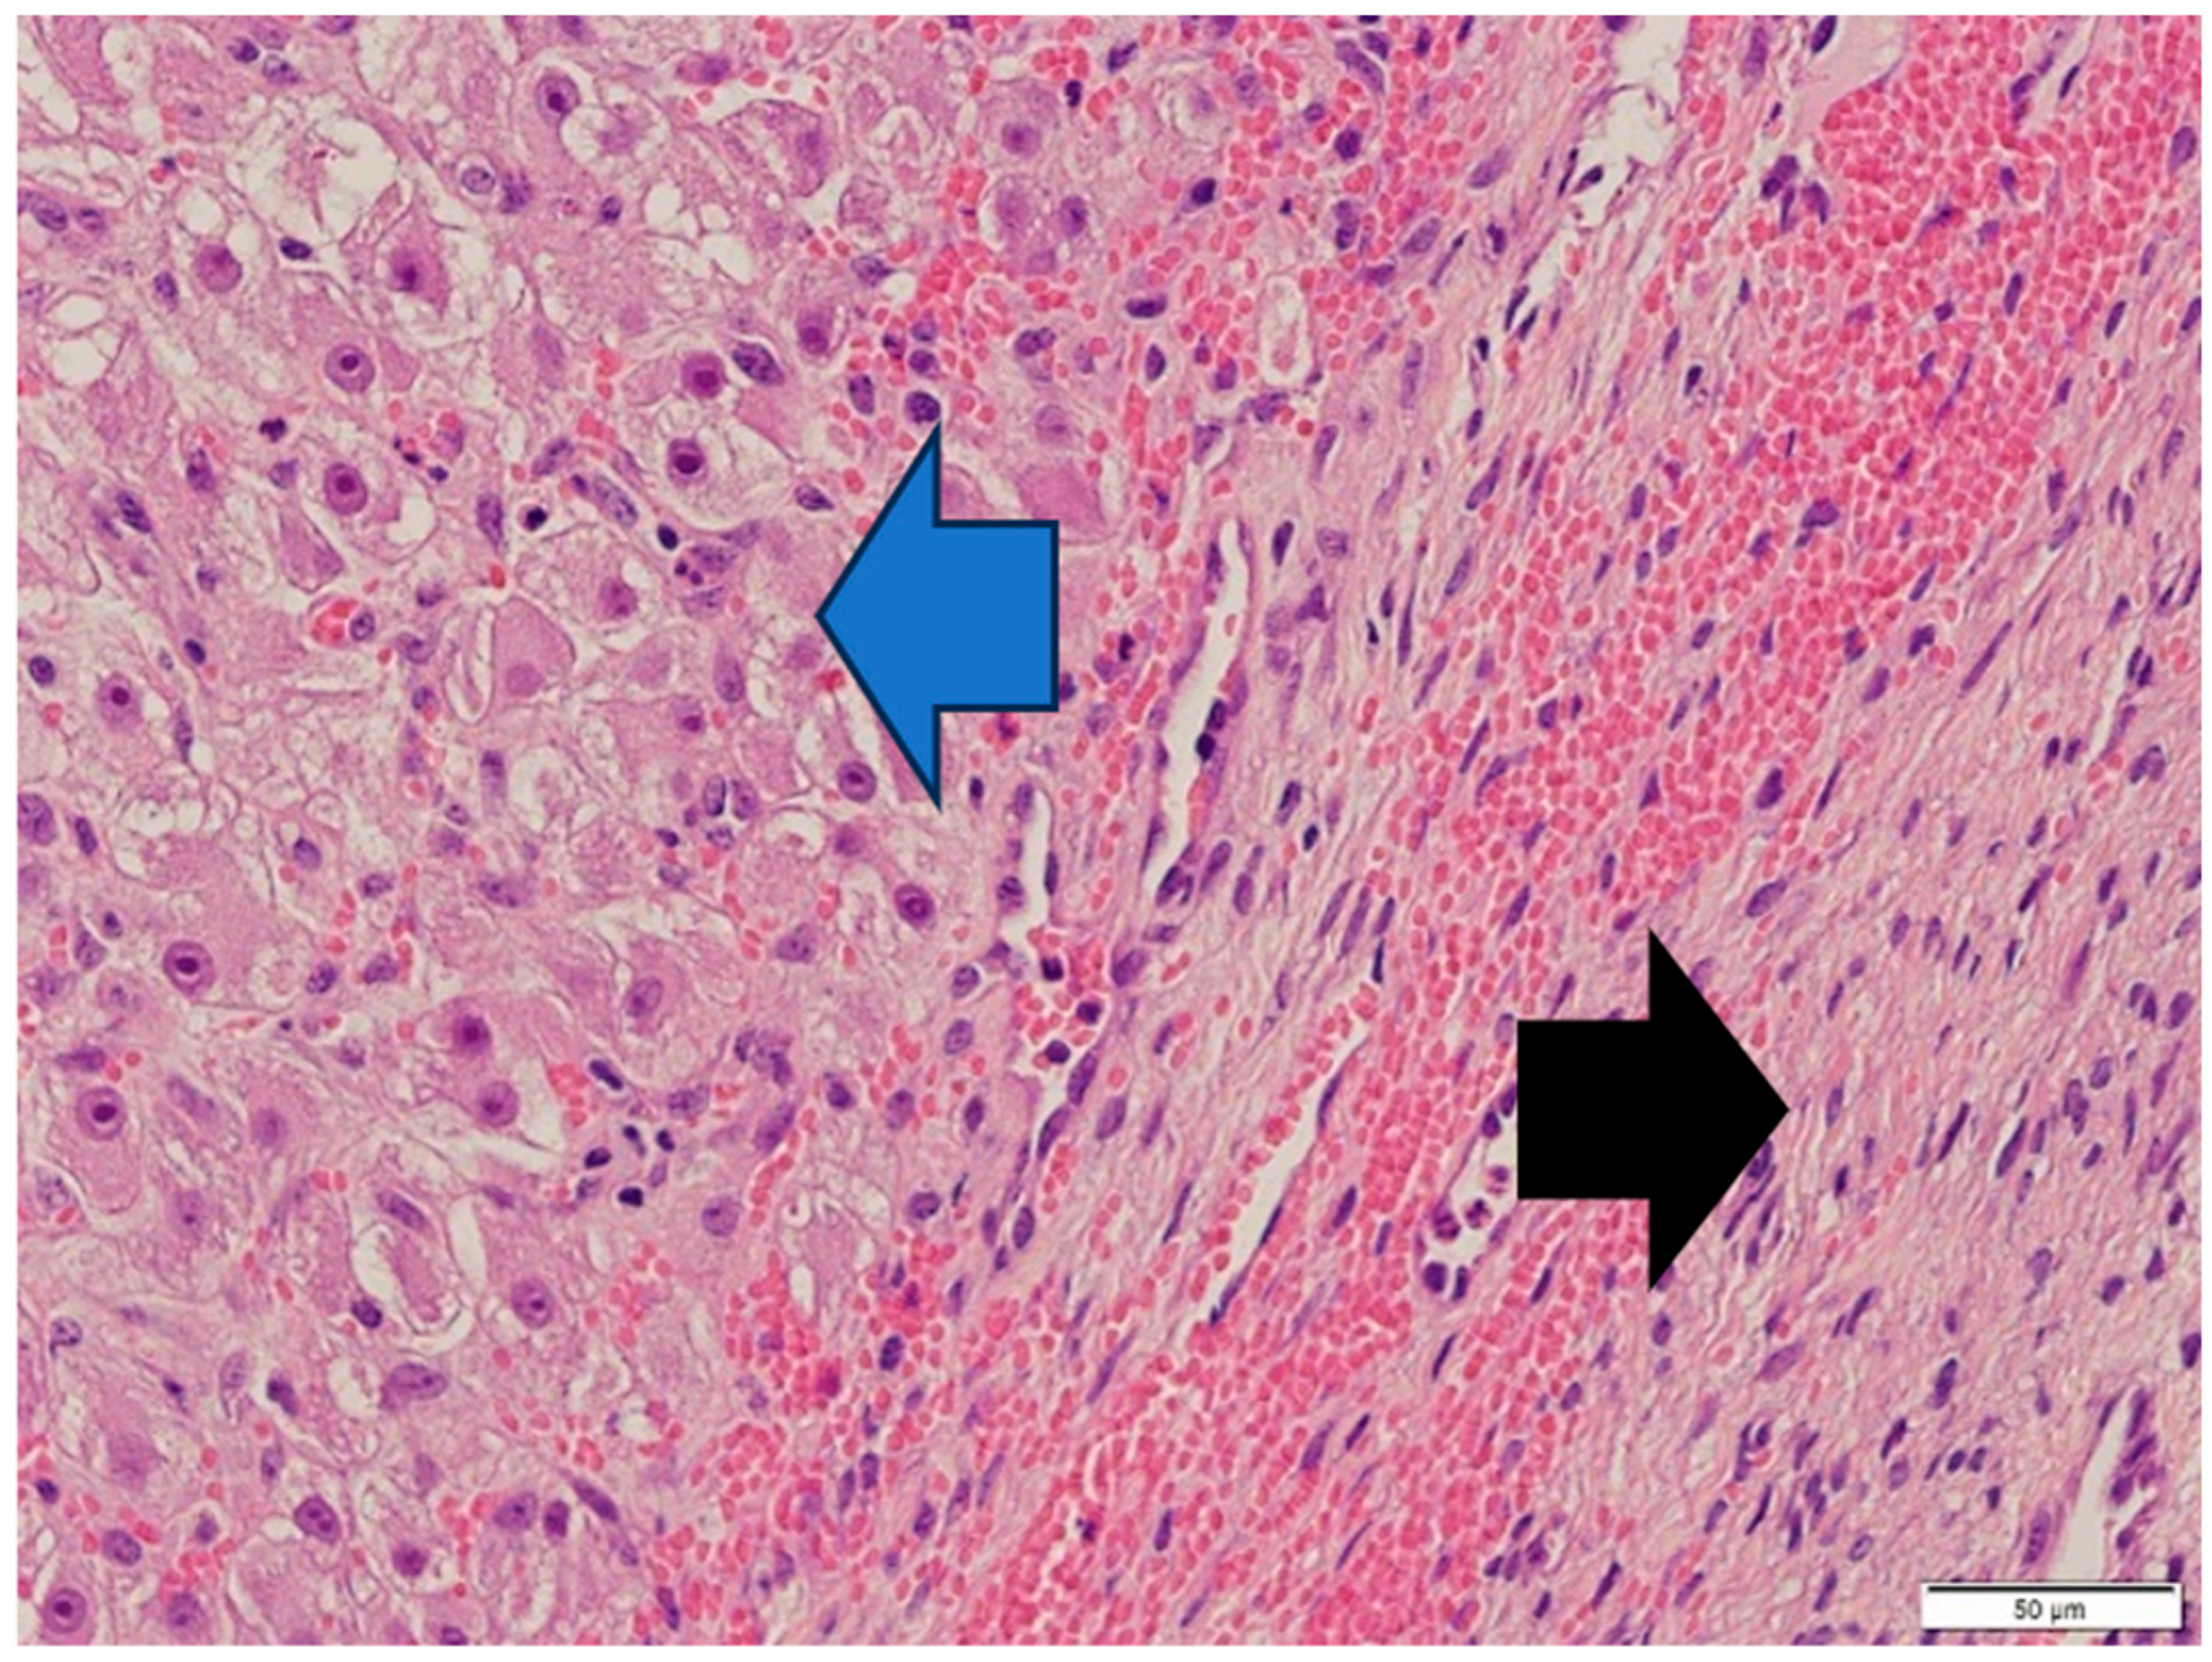

Histologically, both tumor areas were distinctly different from each other (Figure 7 and Figure 8). In the obtained sample for histological examination, the portion of the thecoma was significantly lower (Figure 9). Marked hemorrhage (but not blood-filled lacunae) and very sparse granulation-type connective tissue were observed at the border between both tumor tissues (Figure 10). Hemorrhagic blood masses infiltrated a larger part of the thecoma tissues. A single cystic structure lined with columnar epithelium was found in the hemorrhagic zone, with a very sparse amount of mucus-like material in the lumen (Figure 11).

Thecoma cells had changed the nucleus/cytoplasm ratio in favor of cytoplasm (cytoplasm of thecoma cells was very abundant). The cytoplasm of thecoma cells was irregular in shape and amount, with distinct borders and different sizes and amounts of vacuoles. Nuclei were large, with moderate size and shape variation and large, irregular size nucleoli (macronucleoli) (Figure 12). The mitotic rate was moderate in thecoma tissues—10 normal mitoses per 10 fields at 400 magnification (Figure 13).

Figure 8. Thecoma: population of cells showing ovoid to round nuclei and pale gray abundant oval, round cytoplasm. The distinct large nucleolus inside the nucleus is present (blue arrow). HE, 200× magnification. Black arrow—part of fibroma.

Animals 14 01307 g008

Figure 10. Marked hemorrhage (but not blood-filled lacune) and very sparse granulation-type connective tissue were observed at the border between both tumor tissues. HE, 200× magnification.

Animals 14 01307 g010